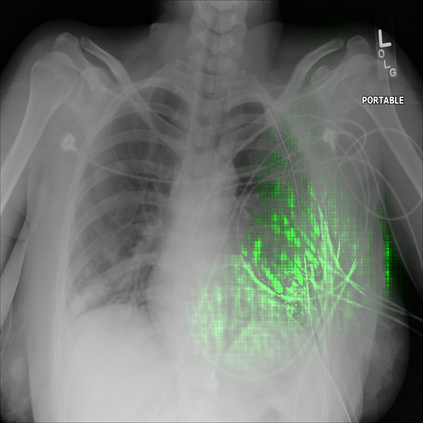

With the ongoing rise of machine learning, the need for methods for explaining decisions made by artificial intelligence systems is becoming a more and more important topic. Especially for image classification tasks, many state-of-the-art tools to explain such classifiers rely on visual highlighting of important areas of the input data. Contrary, counterfactual explanation systems try to enable a counterfactual reasoning by modifying the input image in a way such that the classifier would have made a different prediction. By doing so, the users of counterfactual explanation systems are equipped with a completely different kind of explanatory information. However, methods for generating realistic counterfactual explanations for image classifiers are still rare. Especially in medical contexts, where relevant information often consists of textural and structural information, high-quality counterfactual images have the potential to give meaningful insights into decision processes. In this work, we present GANterfactual, an approach to generate such counterfactual image explanations based on adversarial image-to-image translation techniques. Additionally, we conduct a user study to evaluate our approach in an exemplary medical use case. Our results show that, in the chosen medical use-case, counterfactual explanations lead to significantly better results regarding mental models, explanation satisfaction, trust, emotions, and self-efficacy than two state-of-the-art systems that work with saliency maps, namely LIME and LRP.